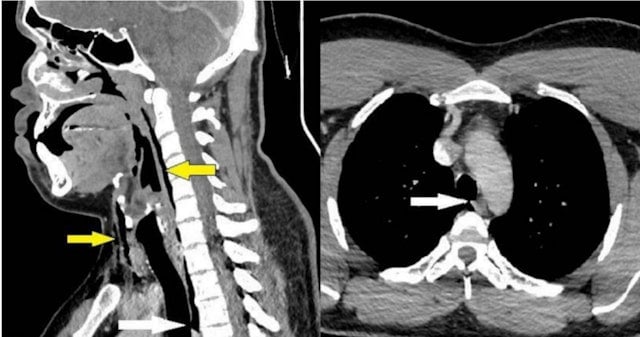

После пальпации пациента врач обнаружил хруст в горле и ограничение подвижности, поэтому немедленно назначил компьютерную томографию. Результаты показали наличие у мужчины разрыва трахеи размером 2x2x5 мм и пневмоторакса.

Медицинский персонал больницы отметил, что повреждения трахеи часто возникают в результате травм, например, от воздействия острых или тупых предметов, а состояние мужчины, известное как «спонтанная перфорация трахеи», на сегодняшний день не было обнаружено.

Медицинский персонал пришел к выводу, что травма была вызвана закрытием трахеи при чихании, в результате чего давление в трахее быстро возрастало, «эквивалентно взрыву».